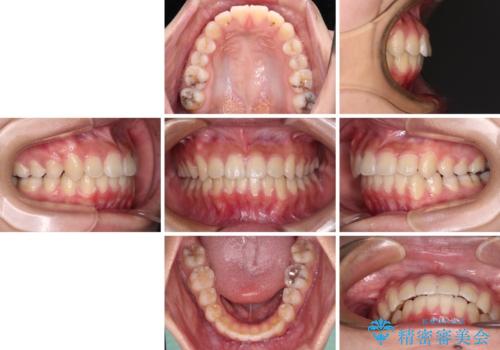

- 下顎の前突感と前歯の叢生を気にして来院された患者様です。

下顎前方位の骨格のため、下顎歯列に対して上顎歯列の幅が狭くなっていました。

急速拡大装置を用いて上顎骨を側方に拡大し、上顎の叢生を解消するとともに下顎歯列拡大により下顎の叢生も解消することとしました。

急速拡大装置使用直後は著しいスペースが正中に発現するため、ワイヤー矯正を行いますが、今回は治療期間を短くしたいとのことで、上下全体をワイヤー装置にて矯正治療することとしました。

上顎骨を拡大しない場合には、奥歯に咬みにくさが残ったり、下顎前歯の歯肉退縮や口元の突出感などが出たりと、妥協的な仕上がりとなります。